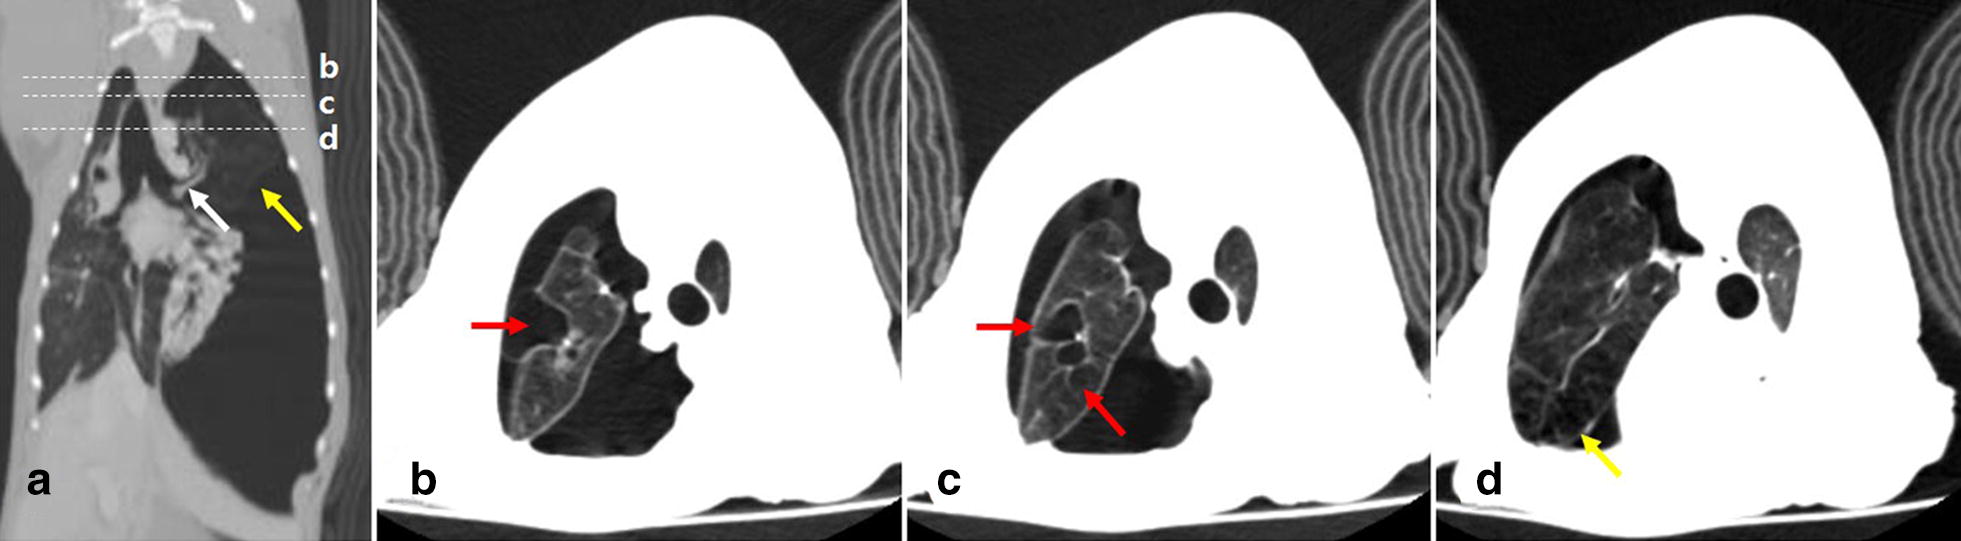

Fig. 2.

Post-contrast dorsal (a) and transverse (b–d) computed tomography scanning images of the thorax after emergent thoracocentesis. a Large volume of air is still identified in the left hemithorax. The left cranial lung lobe is hyperlucent and emphysematous with scant vascular markings (yellow arrows). Left cranial bronchus does not divide into cranial and caudal parts, and only the single lobar bronchus is identified in the left cranial lung lobe (white arrow). The white dotted lines and the lowercase letters b, c, and d represent the sections corresponding to the transverse images of b–d respectively. b–d Several round thin-walled pulmonary bullae of various sizes (red arrows) are observed in the hyperlucent and emphysematous left cranial lung lobe (yellow arrow)